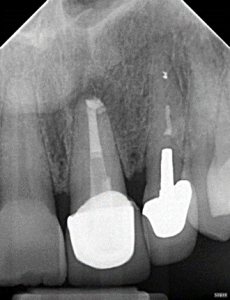

Clinical Cases